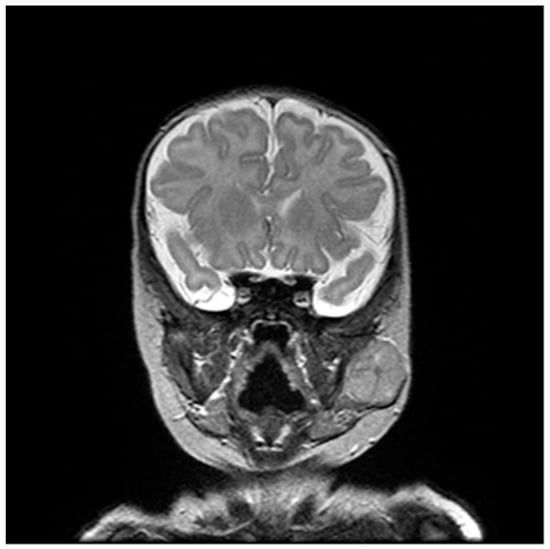

2. Case Presentation

2.1. Diagnosis